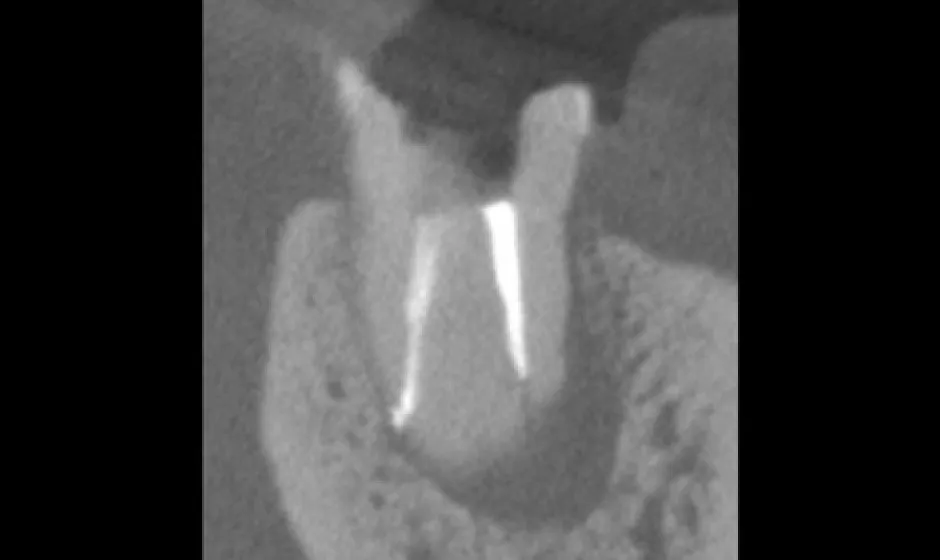

できるだけ歯を守るために、削る量を抑え、神経を残せる可能性も視野に入れながら治療方針を検討します。

歯科用CTで状態を立体的に把握し、必要に応じてマイクロスコープを用いて細部まで確認しながら処置を実施。見えにくい部分ほど丁寧に対応することで、治療精度を高め、再治療のリスクをできる限り減らすことにもつなげます。 -

01精密根管治療

「抜くしかない」と言われた歯でも、根の中の感染を適切に抑えられる治療技術があれば、歯を残せる可能性があります。根管は非常に細く複雑で、わずかな取り残しが痛みや腫れの再発につながることもあるため、当院では必要に応じてCTやマイクロスコープを活用し、原因を見極めながら丁寧に処置を進めます。

大杉歯科医院が大切にしているのは、早く終える治療ではなく、歯を守る治療。津市で、できるだけ天然歯を残したい方の選択肢になれるよう取り組んでいます。症例1